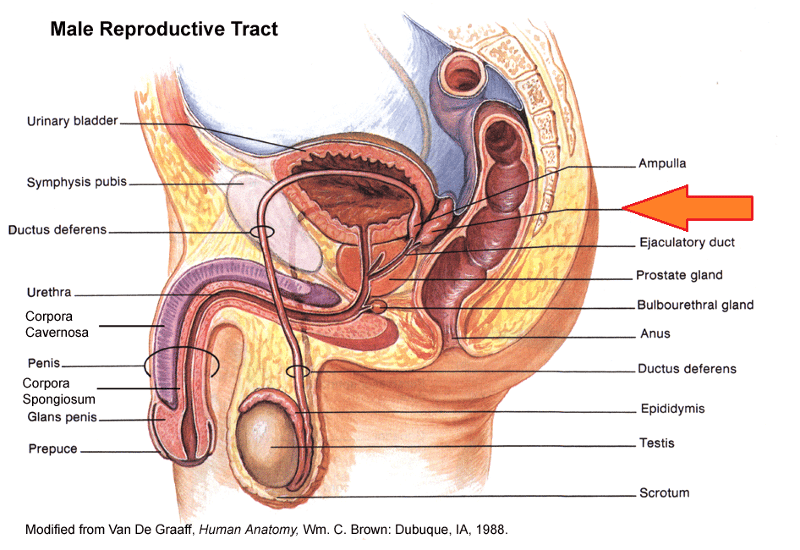

Bulbourethral gland (male)

Corpora cavernosa (pl.) Corpus Cavernosum (s.)

Corpus Spongiosum

Ejaculatory Duct

Epididymis

External urethral orifice (male)

Glans penis

Prepuce (=foreskin)

Prostate gland

Prostatic/spongy urethra (males)

Scrotum

Seminal vesicle

Seminiferous tubule

Testis (s.) Testes (pl.)

Ureter

Urethra

Urinary Bladder (male)

Vas deferens (=ductus deferens)